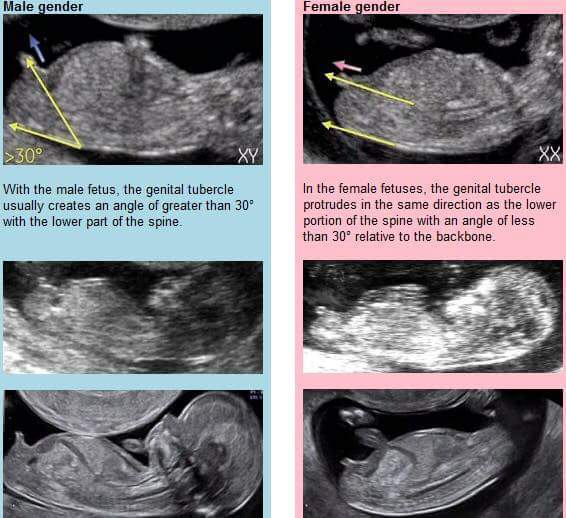

I really don't understand which bit you are meant to be looking at for nub theory Blush Have been staring intently at our scan this evening and still can't figure it out!

This may help...

I'm not even sure if the nub is visible on my scan photo to be honest.

I don't think ours is visible - I couldn't work out what I was meant to be looking at even after looking at pics like that! Blush